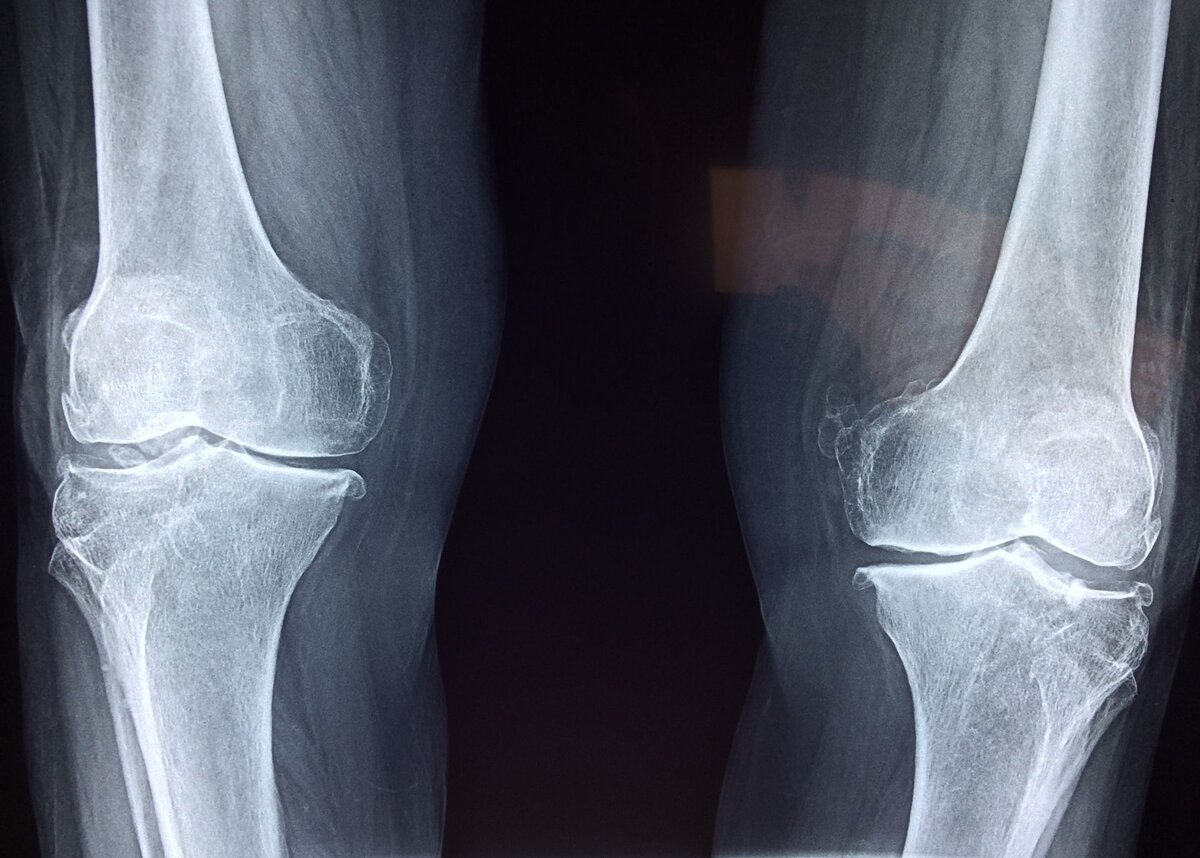

Рентгеновский снимок суставов — как они устроены?

Сустав образуется при соединении двух или более костей. Движение происходит за счет окружающих его мышц, сухожилий и связок. Внутри находится специальная синовиальная жидкость и хрящ, которые обеспечивают амортизацию сустава и регулируют нагрузку.

Когда синовиальной жидкости в суставе становится недостаточно, основную нагрузку на себя берут хрящи. Со временем из-за трения друг об друга, хрящи истончаются и повреждаются. В результате из-за повреждения тканей вырабатывается все меньше синовиальной жидкости, хрящи продолжают разрушаться, что постепенно сказывается на здоровье костей.